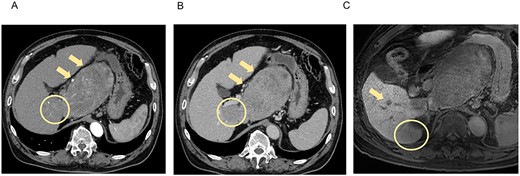

Histopathological findings showed extensive necrosis and hemorrhage of the tumors, probably because of LEN and TACE. One of the S1 tumors was a well to poorly differentiated HCC with a total size of 135 × 80 mm and viable lesion size of 39 × 31 mm (Fig. 3a). The other S1 HCC was a total size of 30 × 25 mm and a viable lesion size of 17 × 2 mm (Fig. 3b), and the S6/7 HCC was a total size of 65 × 40 mm and a viable lesion size of 15 × 2 mm (Fig. 3c). The nodule removed from the Morrison’s fossa was confirmed to be peritoneal dissemination. The noncancerous liver showed mild chronic inflammation in the portal areas with liver cirrhosis (A1, F4).

Photographs showing extensive necrosis and hemorrhage of the resected tumors after LEN and TACE. (A) One of the S1 tumors was a well to poorly differentiated HCC, of which 11% was viable tumor cells. (B) The other S1 tumor was a well to moderately differentiated HCC with 5% viable lesions. (C) The S6/7 tumor was a well to moderately differentiated HCC with 2% viable lesions. Scale bar = 10 mm. S, segment.